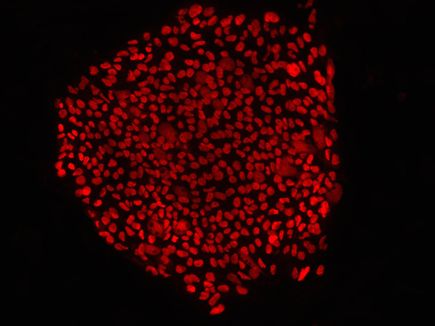

This latest breakthrough overcomes a persistent stumbling block to developing stem cell therapies for human diseases. To conduct this research, the scientists collected skin cells from research subjects, mostly children and a few middle-aged men, with mitochondrial DNA mutations. Next they recovered the nucleus from the skin cells and paired them with healthy donor cytoplasm from an egg. Cytoplasm is the watery material surrounding a cell’s nucleus that contains the mitochondrial DNA. The mitochondria have the specific task of generating energy for the cell. Through this technique, scientists created an embryonic stem cell with healthy mitochondria.

Scientists aspire to use this technique to replace diseased tissue in the future by removing one cell, correcting the mutations, multiplying the cells and reinserting the genetically correct cells into the patient to replace diseased tissue. The nuclear transfer technique is more precise than classic gene therapy. Rather than inserting synthetic genes into patients delivered by viruses, nuclear transfer uses donated healthy mitochondrial genes.